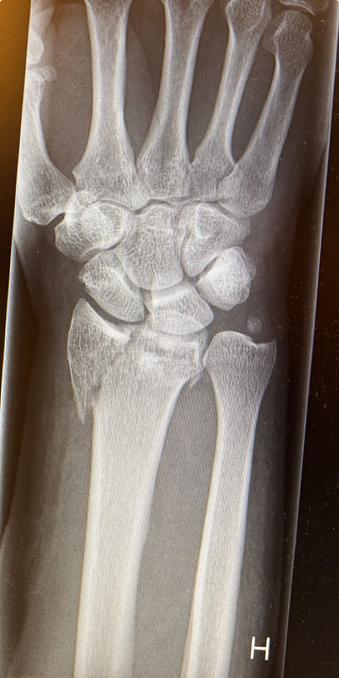

How surgeons fix a broken wrist